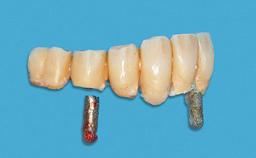

The case concludes with the presentation of the final prostheses at the 3-year follow-up, demonstrating a stable and pleasing soft- and hard-tissue situation.

Prosthesis Type | FDP |